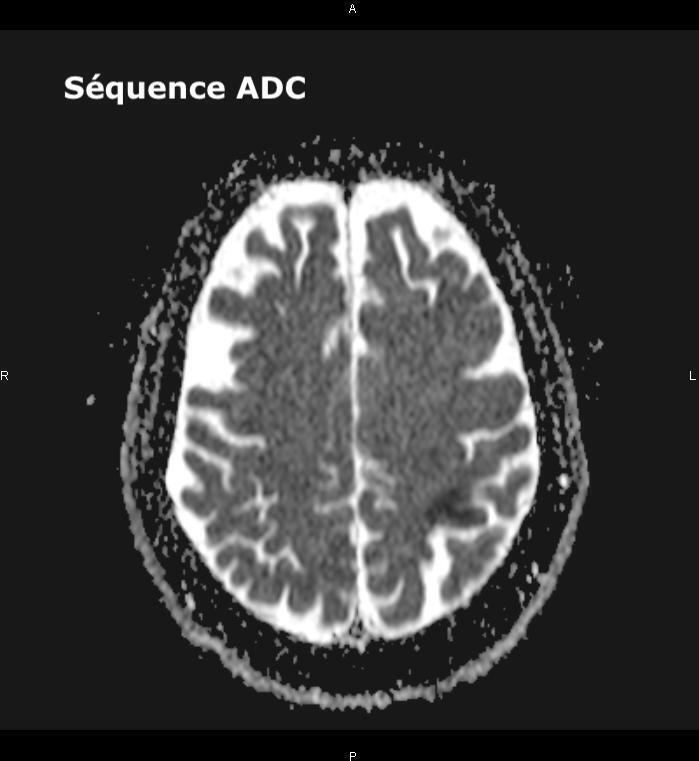

Un ou plusieurs déficits neurologiques (ataxie cérébelleuse, paralysie faciale) d’apparition soudaine (et le plus souvent d’emblée maximale), focale (tous les signes peuvent ici être expliqués par l’atteinte d’un seul territoire artériel) doivent faire évoquer le diagnostic d’AVC, et doivent conduire à une imagerie cérébrale rapidement.